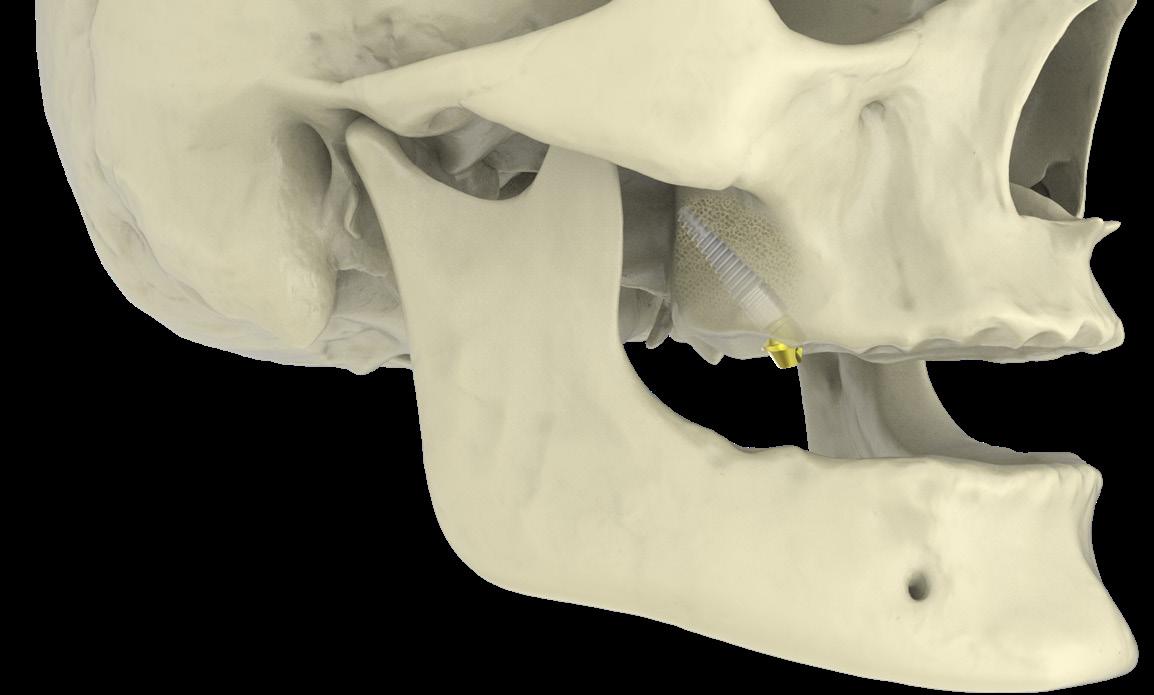

Implanturile zigomatice Southern Implants (fig. 1) oferă soluții sigure pentru reabilitarea maxilarelor cu atrofie severă, prin ancorare în osul zigomatic, putând elimina necesitatea grefelor osoase în multe cazuri selectate. Disponibile în lungimi de 30–60 mm, cu opțiuni Co-Axis® 55° pentru corecția angulației, asigură stabilitate și emergență protetică optimă. Suprafața SInergy™ sprijină osteointegrarea, iar zona MSC (Machined Surface Coronal) reduce riscul de periimplantită. Selectarea se realizează conform protocolului

ZAGA, pentru o adaptare precisă la anatomia pacientului.

Implanturile pterigoidiene

Southern Implants (fig. 2) sunt concepute pentru inserare la un unghi de 45–60°, oferind ancorare sigură în osul cortical pterigoidian și stabilitate ridicată chiar și în cazurile de atrofie severă. Designul conic, cu vârf îngust și filet auto-tăietor, permite inserție controlată în os cortical dens, iar încărcarea imediată este posibilă în funcție de stabilitatea primară obținută. Conexiunea Deep Conical asigură etanșeitate între implant și componenta protetică, iar suprafața tratată SInergy™

sprijină osteointegrarea rapidă și durabilă.